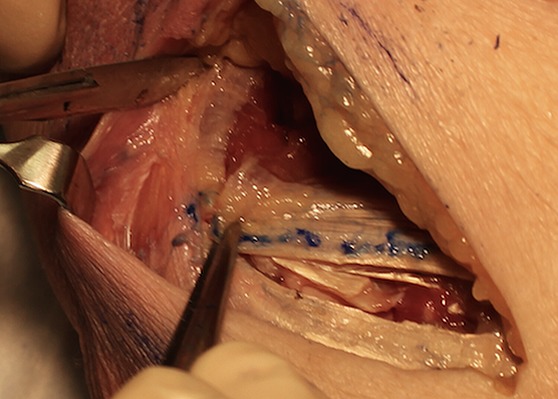

Figs. 9-A and 9-B Capsulotomy in the EDC splitting approach.

Fig. 9-A.

The lateral elbow capsulotomy is performed anterior to the equator of the capitellum in line with the EDC split exposing the radiocapitellar joint. LUCL = lateral ulnar collateral ligament.

Fig. 9-B.

An anteriorly placed capsular retractor demonstrates the increased exposure to the anterior radial head. Compare with the modified Kocher exposure of the radial head in Figure 4-B.